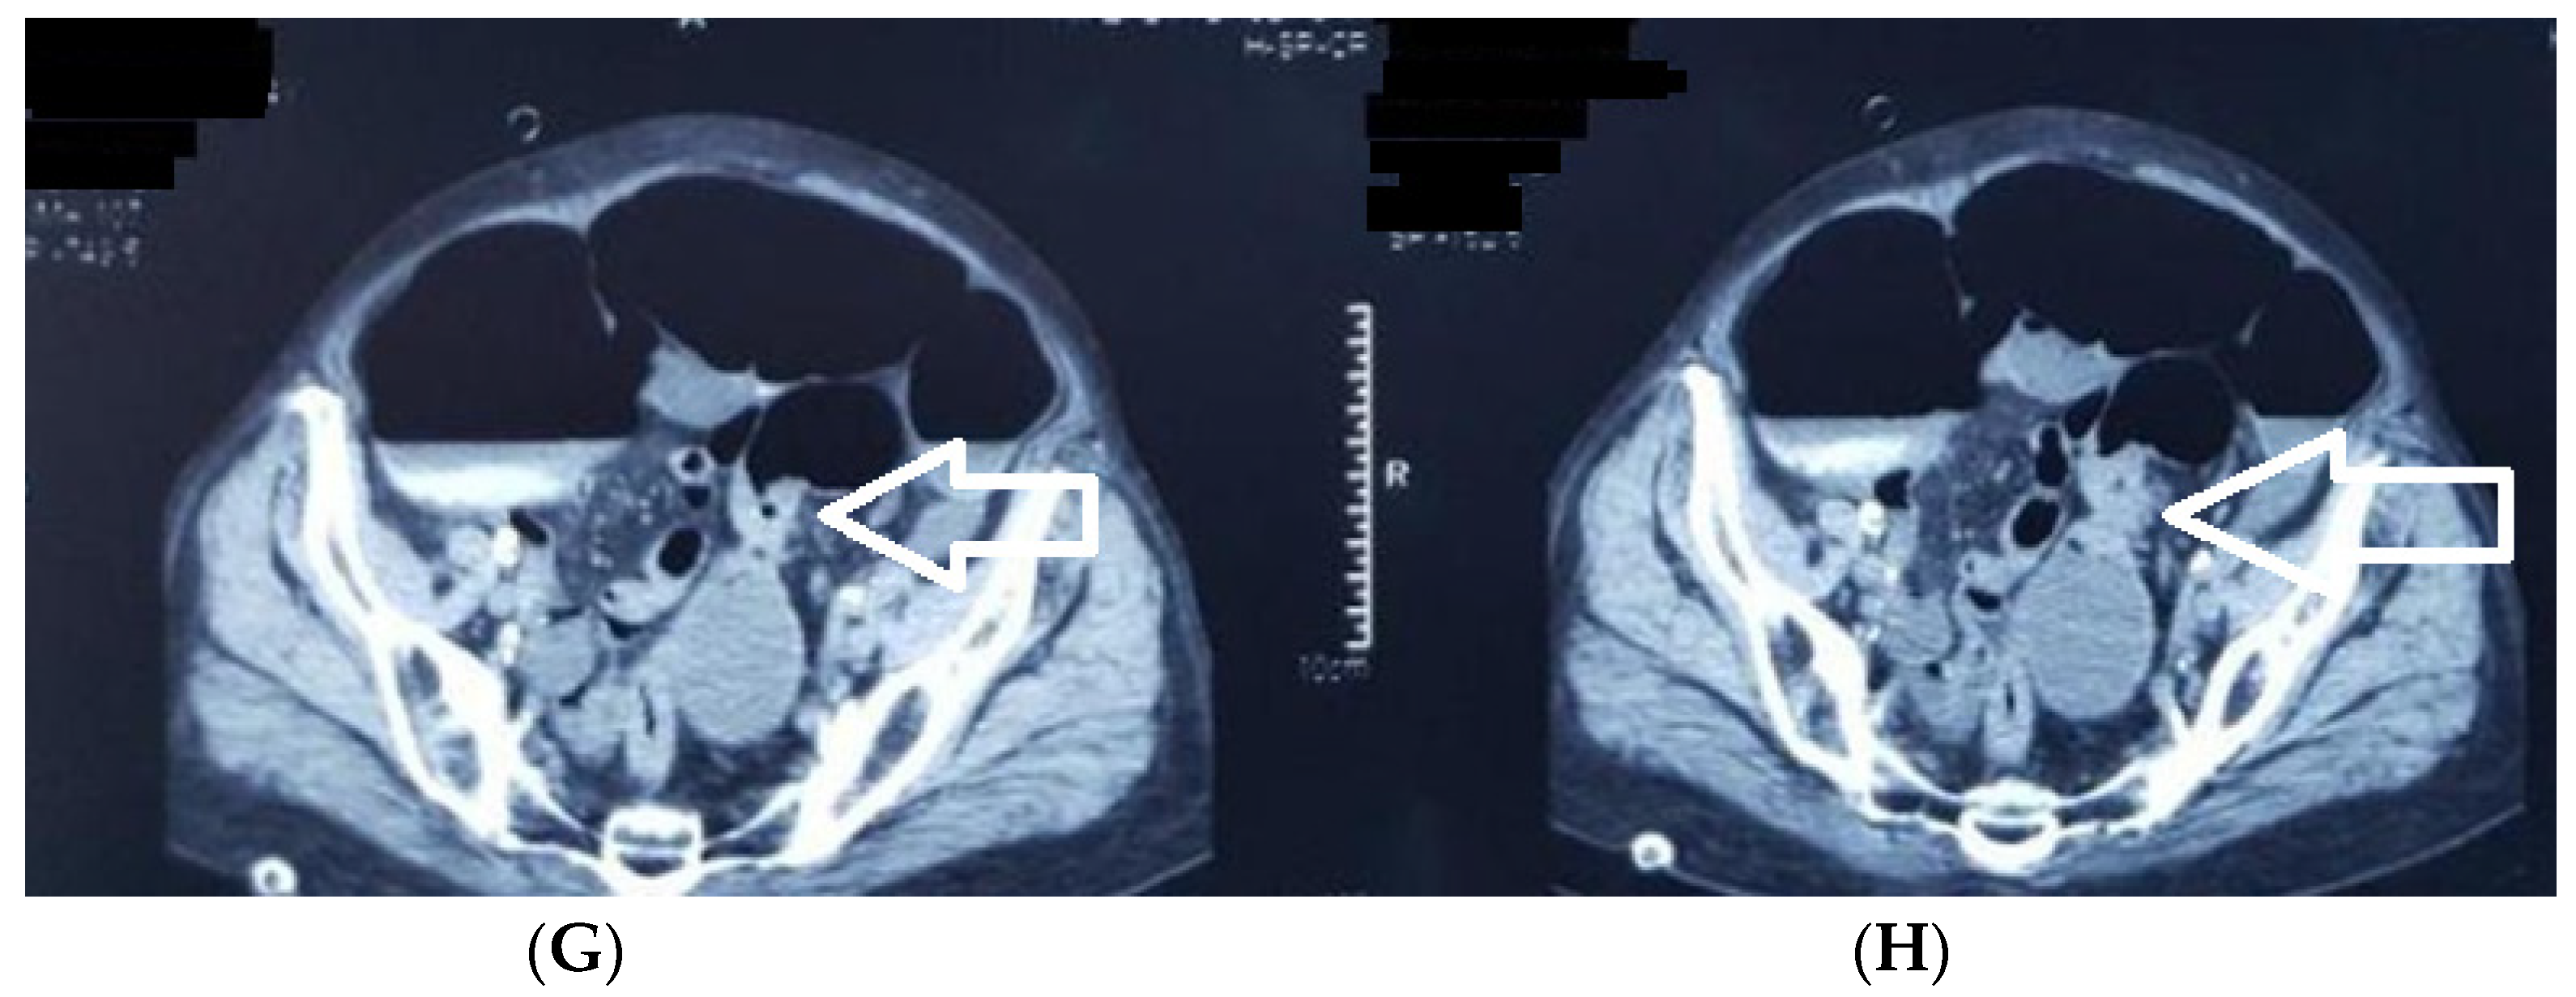

- rectum (including the rectosigmoidian junction (Figure 10), superior rectum, medium rectum, inferior rectum and anus), consisting of 67 patients, 43.8% of the study group.